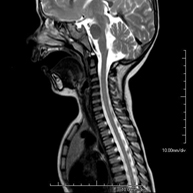

- Cervical spine MRI

This non-invasive diagnostic procedure uses an electromagnetic field and radio waves (from a transmitter and receiver) to acquire high-definition anatomical images of the cervical spine. It is a radiation-free procedure. Indicated for: trauma, spinal degeneration, hernias.

- Thoracic spine MRI

This non-invasive diagnostic procedure uses an electromagnetic field and radio waves (from a transmitter and receiver) to acquire high-definition anatomical images of the thoracic spine. It is a radiation-free procedure. Indicated for: trauma, degenerative problems, hernias, tumours.

- Cervical + thoracic spine MRI

This non-invasive diagnostic procedure uses an electromagnetic field and radio waves (from a transmitter and receiver) to acquire high-definition anatomical images of the cervical and thoracic spine. It is a radiation-free procedure. Indicated for: trauma, spinal degeneration, hernias.